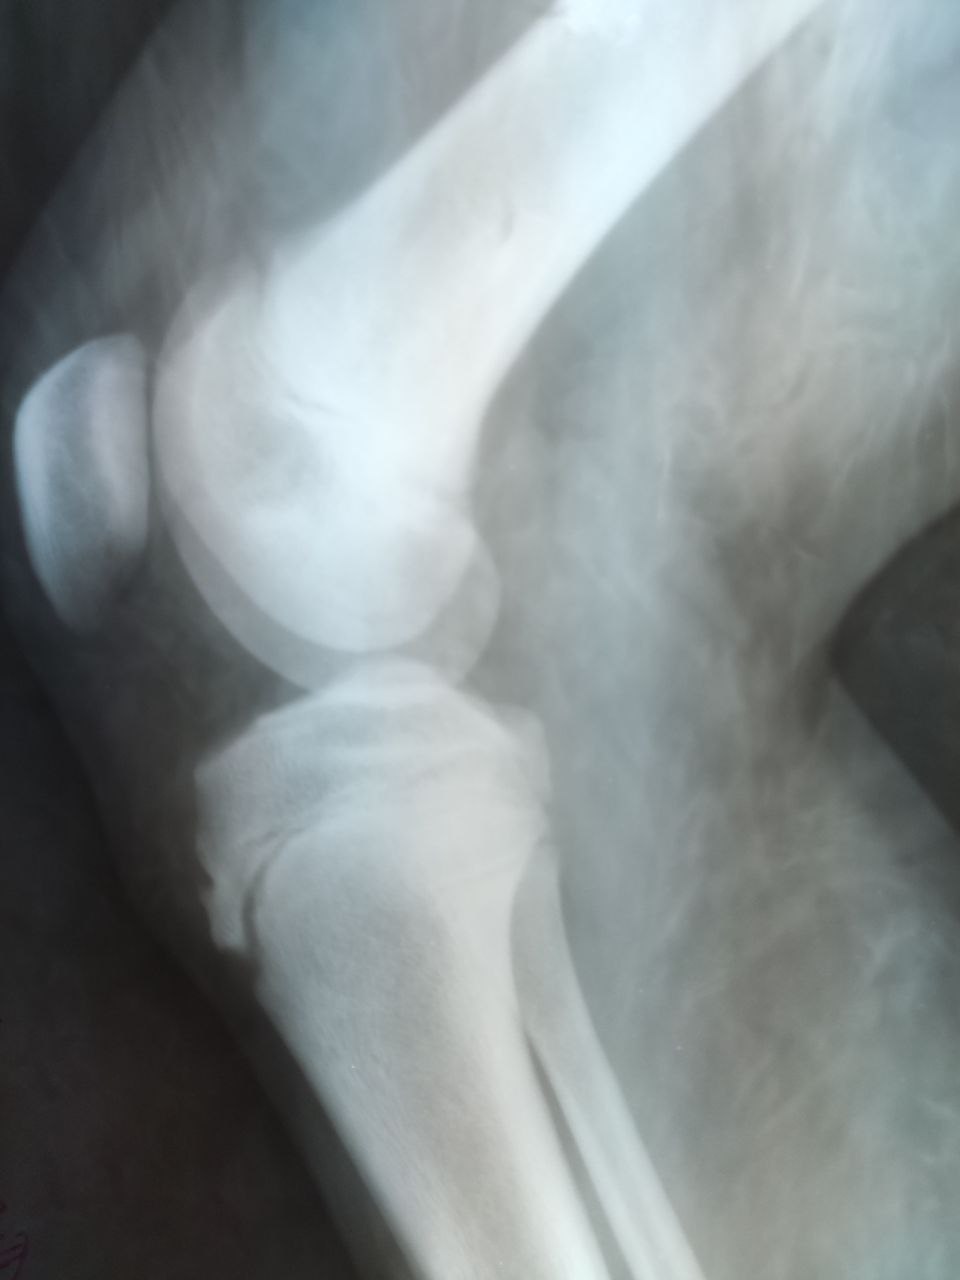

Ребенок 14 лет, жалобы на "образование под коленом". Что это ? Просто экзостоз?

Остеохондрома

Т.е. костнохрящевой экзостоз

Доброго дня! Подскажите пожалуйста, как правильнее назвать вот эти линейные кальцинаты в проекции суставнлй щели у возрастных пациентов? Или просто в заключении подвести суммарно как проявления артроза?

Хондрокальциноз

Красивый (студенческий) хондрокальциноз.

Полезно искать подобные, когда они короткие.